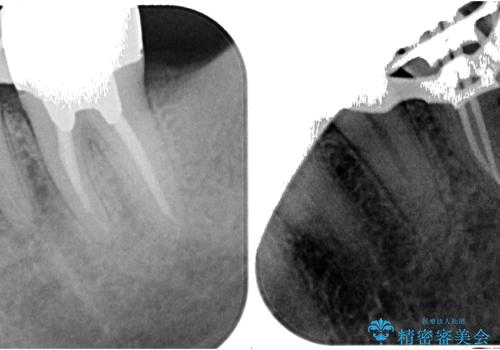

レントゲン写真などで診査を行ったところ、不適合な詰め物の周りから炎症が波及し、神経組織が壊死していると診断されました。

まずは根管治療を行い、症状が消退したことを確認してオールセラミッククラウンにて補綴治療を行うこととしました。

根管治療を行った奥歯は、再発防止や残された歯質を守るため、クラウンによる補綴治療が必要となります。